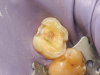

An immediate dentin sealing procedure was performed (Figure 4) and the tooth was prepared for a ceramic onlay restoration. At the subsequent appointment, a lithium-disilicate restoration was bonded to the tooth to allow a homogenous force distribution on the tooth (Figure 5). To prevent excessive wear and nocturnal parafunction, a full-contact permissive splint was indicated for the patient.

Fig 4. Immediate dentin sealing on tooth No. 3.

Figure 4